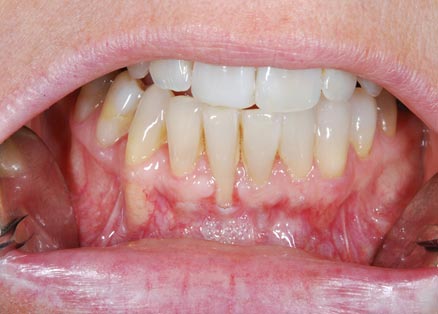

I denti irrecuperabili dell'arcata superiore ed inferiore del paziente di anni 65

sono stati sostituiti da 10 impianti, cioè protesi radicolari endo-ossee che sostengono le protesi fisse superiore ed inferiore.